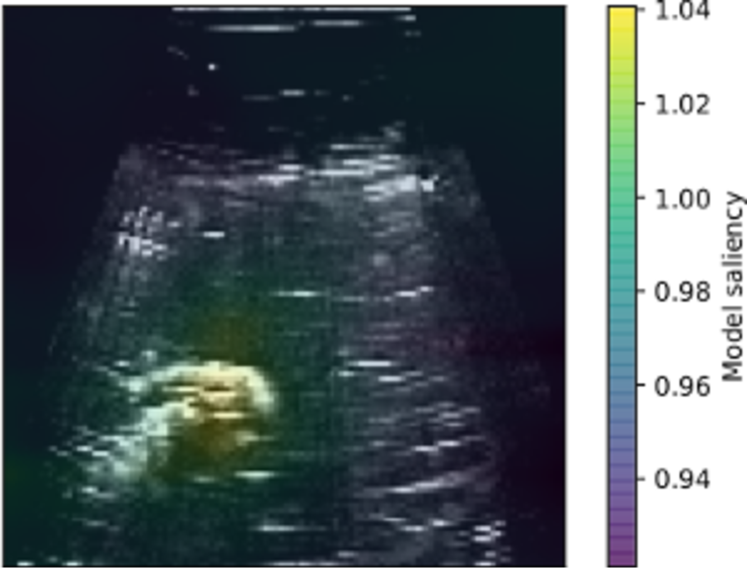

We qualitatively assessed the image regions and features identified using the reward model using saliency maps (Figure 1d), which indicated that the proposed approach has learned to associate the target object with reward.

Trials were repeated 15 times for each approach, alternating between each, and ultrasound gel was replaced after 10 trials. Each trial ran for approximately 5 minutes, and was stopped when the robot pose had converged to a stable point, or after 350 frames had been observed. A high quality ultrasound scan is one in which the contours of the target object stand out as high intensity, where the object is centrally located in a scan, and imaged clearly enough to give some idea of the target object size (see Figure 2).